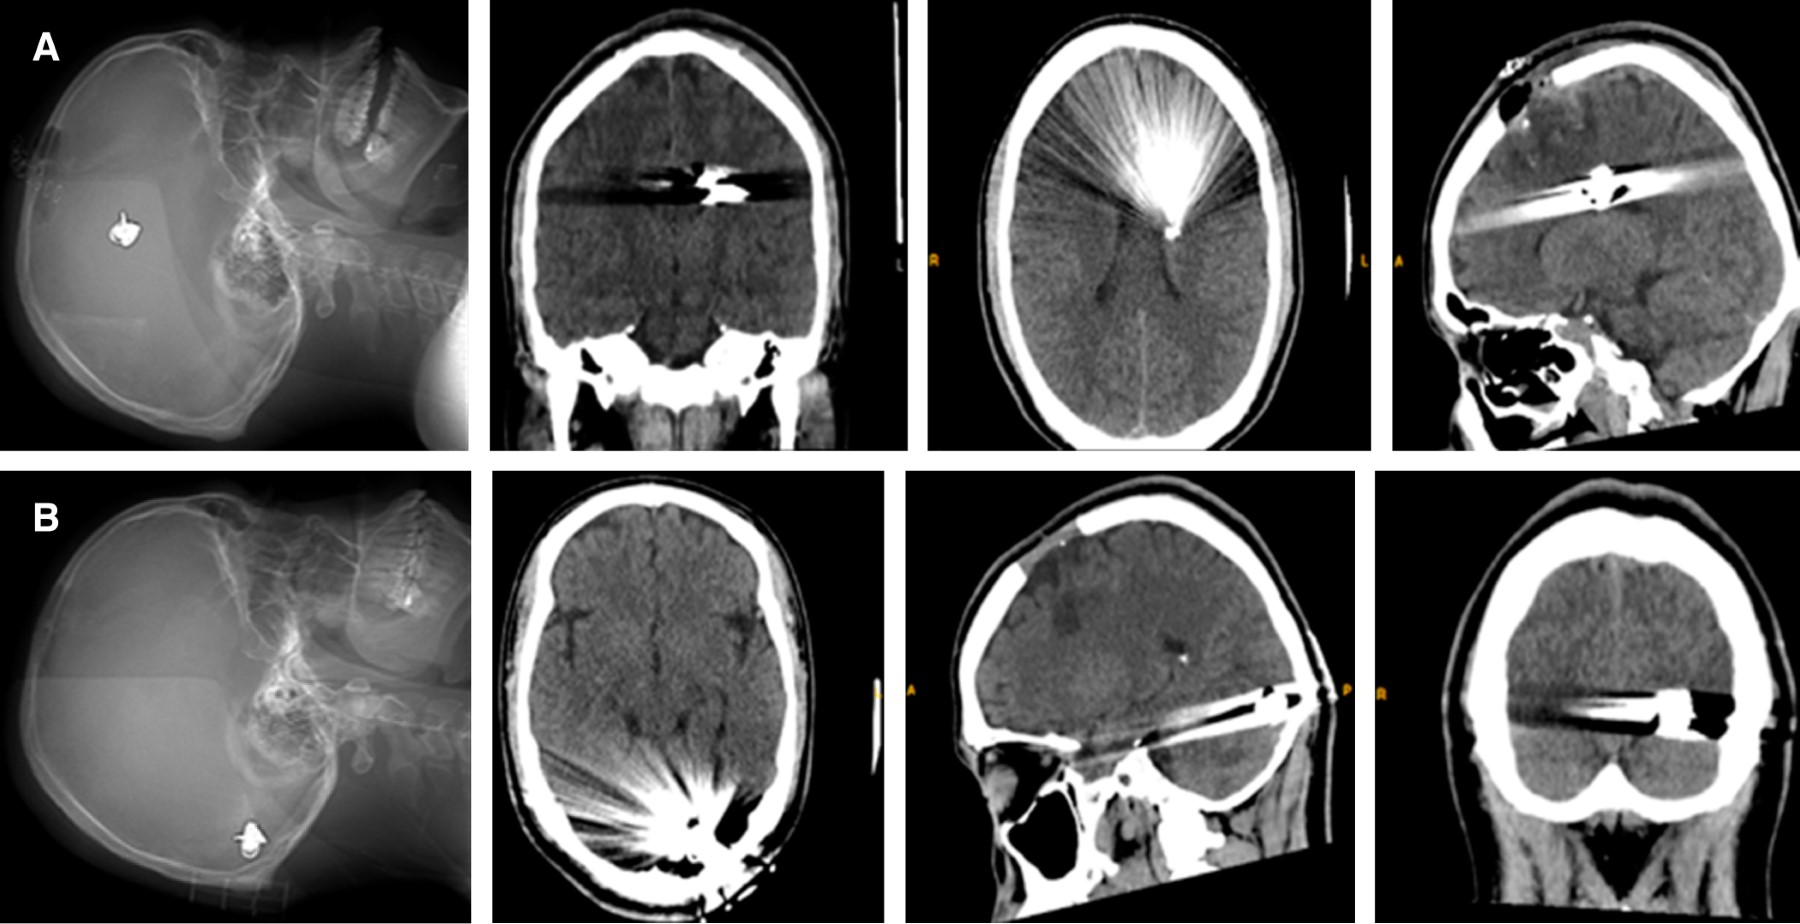

Masculino de 22 años con antecedente de trauma craneoencefálico (TEC) moderado secundario a HPAF frontal izquierda asociado con hematoma subdural y hemorragia intraparenquimatosa (Figura 1), requiriendo esquirlectomía de fractura de bóveda craneana + drenaje de colecciones. Posterior a su estancia hospitalaria es dado de alta con secuelas neurológicas dadas por hemiparesia 4/5 derecha e hipoestesia ipsilateral.

Reconsulta por cefalea de alta intensidad sin mejoría con analgésicos, bradipsiquia y bradilalia, disminución en agudeza visual asociada con fotofobia y fonofobia, por lo que se realiza TAC cerebral evidenciando migración del proyectil a región occipital izquierda (Figura 1). Como estudio complementario se realizan campos visuales electrónicos (Figura 2A) evidenciando amaurosis izquierda con hemianopsia temporal derecha. Por el déficit visual de novo se decide realizar extracción del proyectil guiado por fluoroscopia (Figura 3). En el postoperatorio presenta mejoría gradual de la visión y disminución de cefalea, una vez completado esquema antimicrobiano y rehabilitación intrahospitalaria es egresado.

Seis meses posterior a la extracción del proyectil, el paciente se presenta con mejoría de su estado funcional sin presencia de hemiplejia y mejoría en la sensibilidad. Se realizan campos visuales de control con mejoría de 80% y hemianopsia homónima derecha secuelar (Figura 2B).

Figura 1